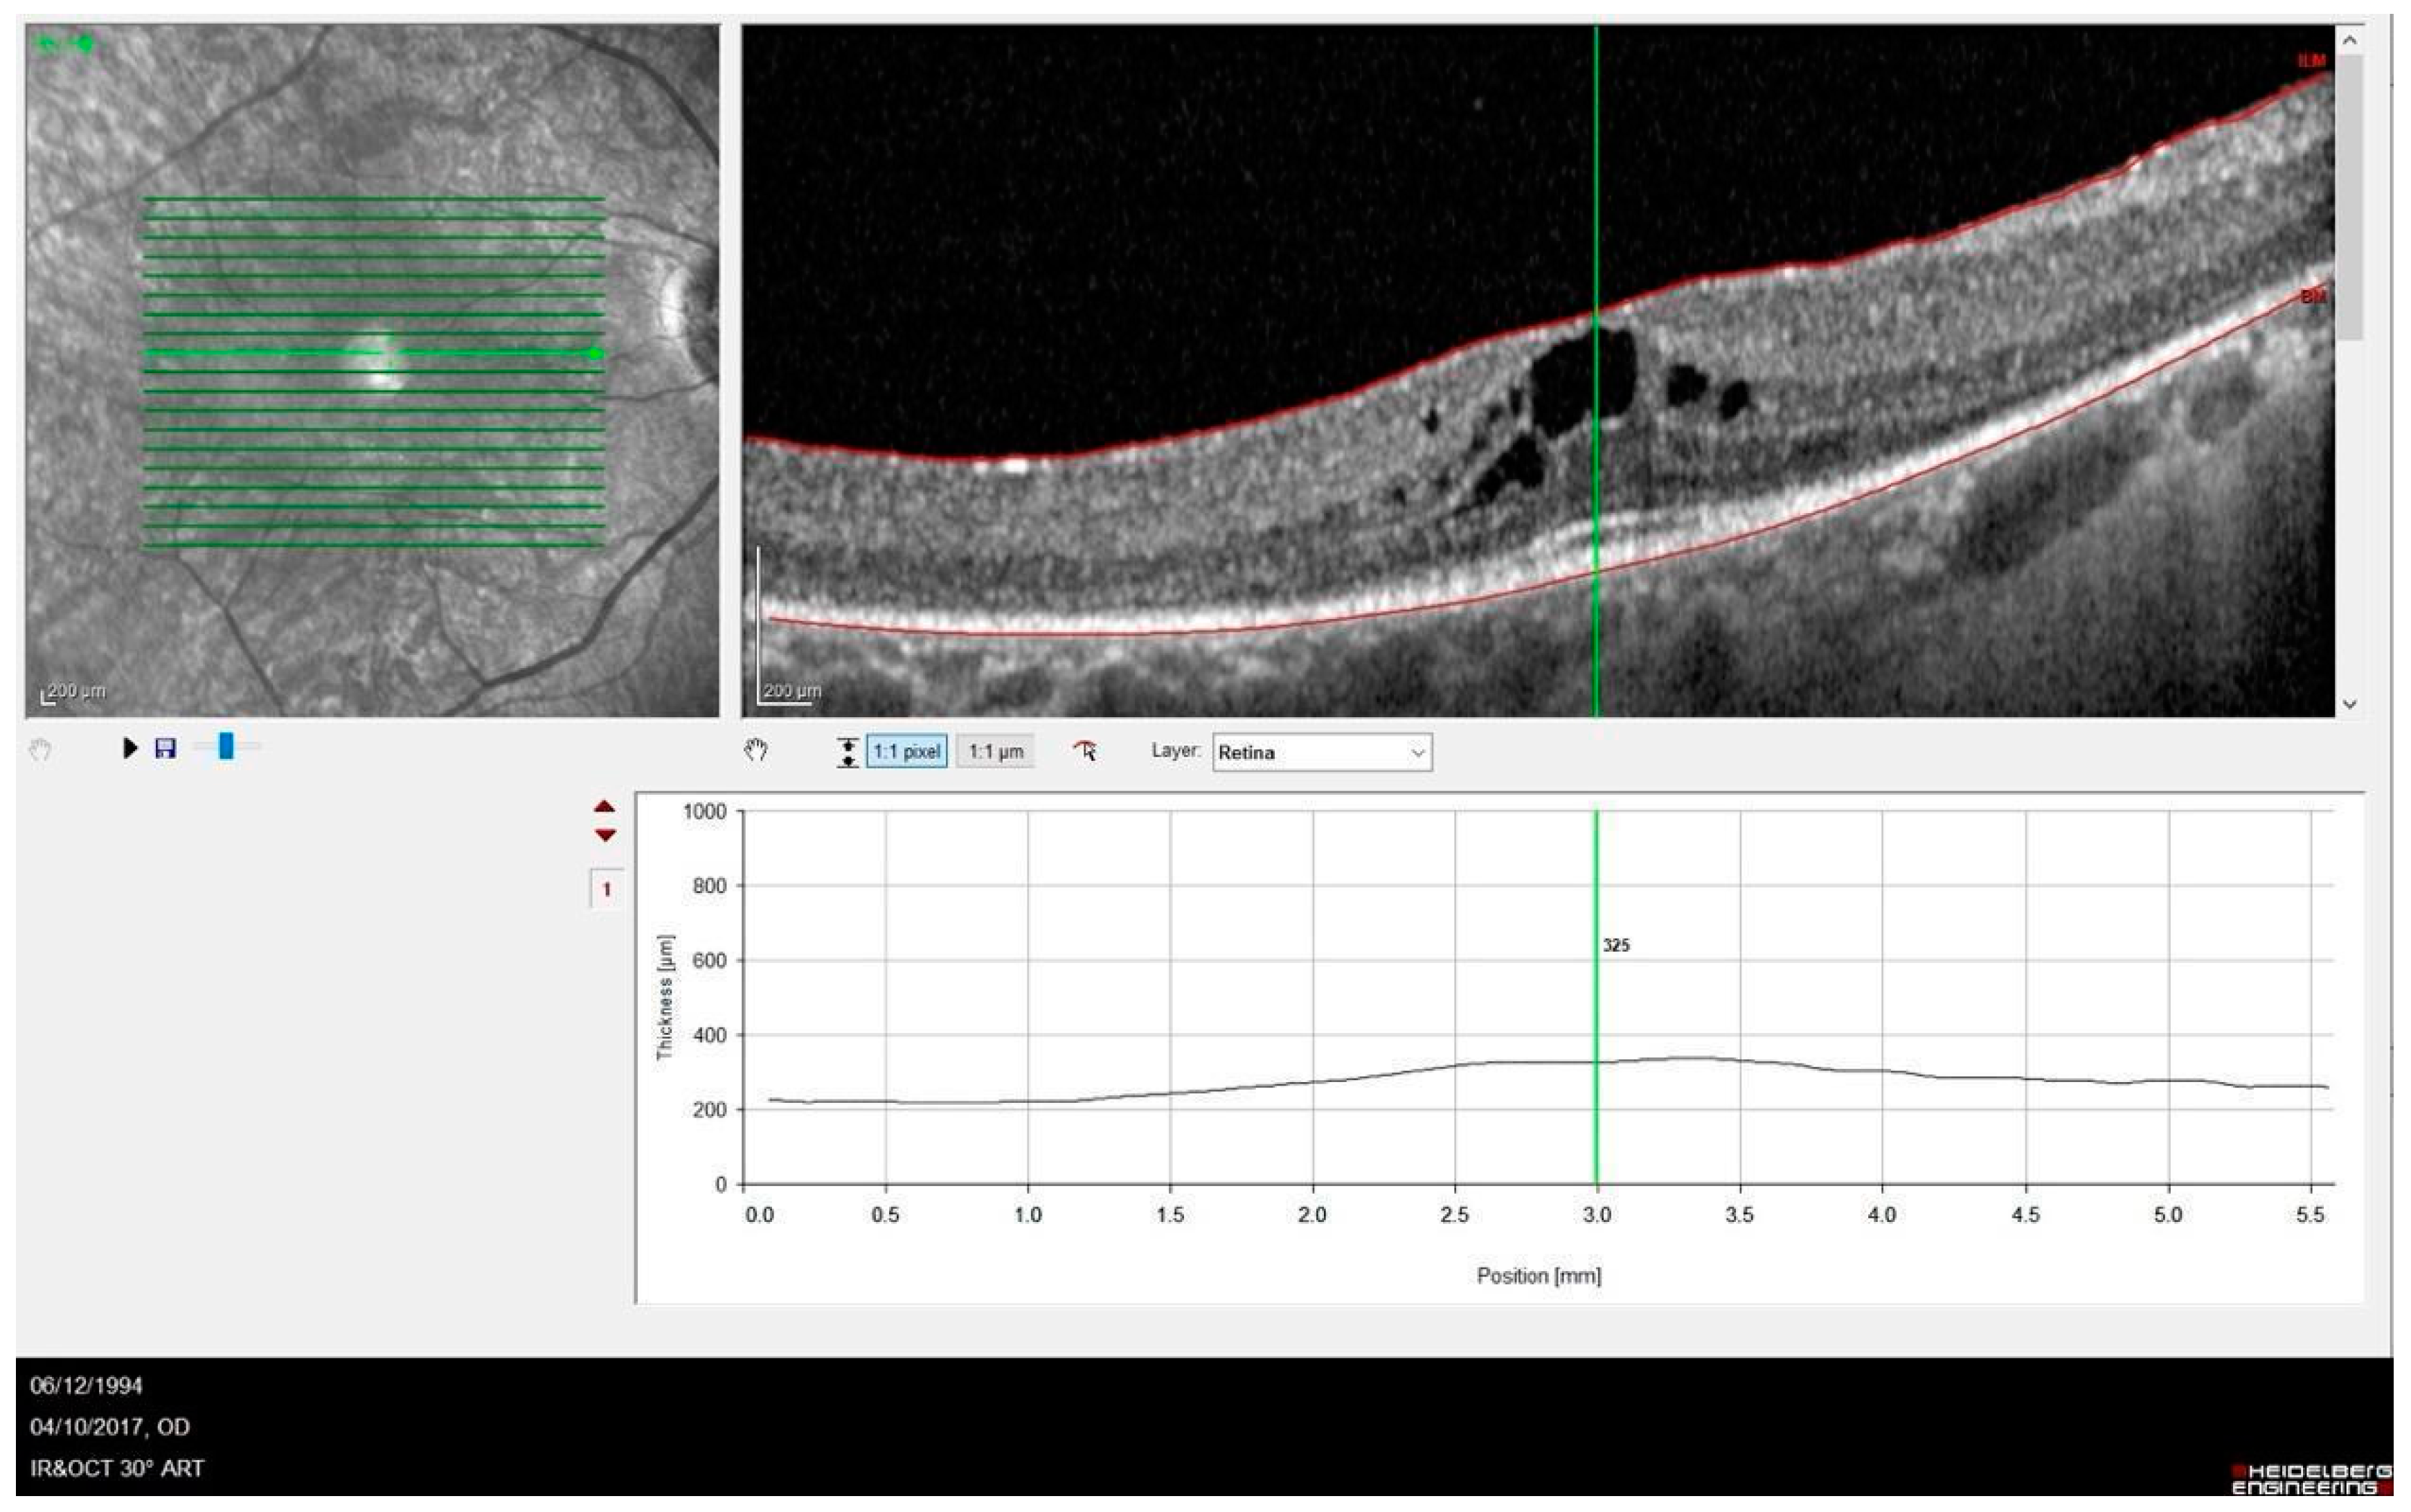

| Patient | Gender | Age | Symptoms at Time of Diagnosis | Age of Symptom Onset | BCVA logMAR (RE; LE) | Genetic Variants |

|---|---|---|---|---|---|---|

| 1 | F | 66 | Reduced visual field | 55 | 0.1; 0.1 | c.2029C>T p.(Arg677*)/WT |

| 2 | F | 58 | Hemeralopia | 4 | HM; HM | c.5962dup p.(Ile1988Asnfs*3)/c.5962dup p.(Ile1988Asnfs*3) |

| 3 | F | 32 | Nystagmus | 2 | HM; 0.7 | c.2019C>T p.Arg677*)/WT |

| 4 | M | 60 | Hemeralopia | 43 | 0.2; 0.5 | c.2019C>T p.Arg677*)/WT |

| 5 | F | 77 | Hemeralopia | 47 | LP; LP | c.2029C>T p.(Arg677*)/WT |

| 6 | M | 52 | Reduced visual field | 48 | 0.1; 0.1 | c.2029C>T p.(Arg677*)/WT |

| 7 | M | 32 | Hemeralopia | 12 | HM; HM | c.1234dup (p.Met412Asnfs*7)/c.1234dup (p.Met412Asnfs*7) |

| 8 | F | 79 | Reduced visual field | 74 | LP; no LP | c.2029C>T p.(Arg677*)/WT |

| 9 | F | 77 | Hemeralopia | 30 | 0.8; 1.0 | c.2029C>T p.(Arg677*)/WT |

| 10 | M | 57 | Reduced visual field | 6 | LP; LP | c.5962dup p.(Ile1988Asnfs*3)/c.5962dup p.(Ile1988Asnfs*3) |